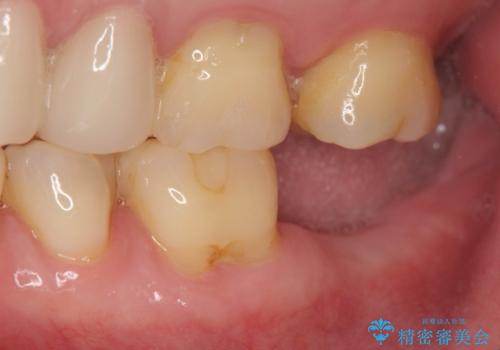

歯からの異臭 虫歯の再発からのインプラント治療

- 「歯から異臭がする。」とのことで相談に来院されました。

X線検査を行ったところ、セラミッククラウン下に虫歯が再発し、歯の破折も認めました。

歯の抜去を行い、骨の造成を含めたインプラントによる咬合機能の回復を図ります。

X線を撮ることで、外から見てもわからない、歯の問題点をより正確に把握することができます。